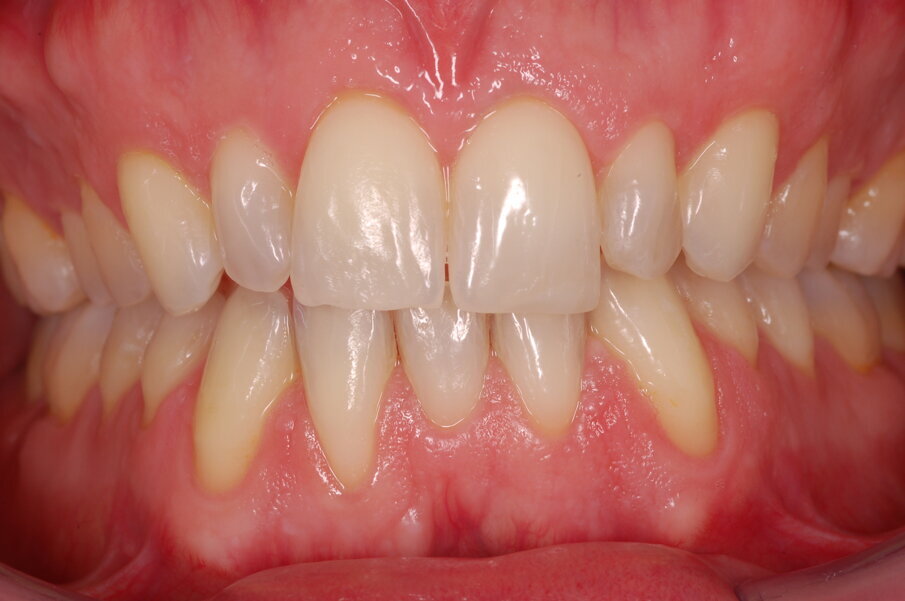

Diagnosi ed eziologia Un uomo sano di 39 anni si è presentato nel nostro studio ortodontico lamentando un aspetto dentale poco attraente e la paura della chirurgia ortognatica proposta da un altro ortodontista. Clinicamente, il profilo del paziente era rettilineo e la vista frontale non mostrava alcuna asimmetria facciale. L’esame funzionale non ha rivelato alcuna deviazione mandibolare o riduzione dei movimenti. Il paziente non aveva dolori articolari e non sono stati rilevati rumori articolari. Era presente una lieve occlusione molare bilaterale di Classe II, un morso aperto e un grave affollamento in entrambe le arcate. L’affollamento era particolarmente grave nell’arcata mandibolare, sebbene mancasse l’incisivo centrale mandibolare destro. Gli incisivi mascellari erano di piccole dimensioni, suggerendo una discrepanza dell’indice di Bolton se fossero stati presenti tutti e quattro gli incisivi mandibolari. Erano inoltre presenti un morso incrociato nella regione dell’incisivo laterale superiore sinistro e una grave rotazione distale del secondo premolare mandibolare sinistro (Figg. 1-8).

Figg. 1-8_Fotografie facciali e intraorali pre-trattamento.

Risultati del trattamento Le fotografie extraorali post-trattamento hanno mostrato il miglioramento dell’estetica del sorriso (Figg. 51-58). È stata ottenuta una solida occlusione bilaterale di Classe I con overjet e overbite normali. Le arcate dentali erano ben allineate e livellate e anche la grave rotazione del secondo premolare mandibolare sinistro è stata corretta solo con gli allineatori. La valutazione cefalometrica post-trattamento (Fig. 59) ha mostrato un miglioramento della posizione anteroposteriore degli incisivi mandibolari (Li-APog: 2,21 mm), pur mantenendo l’altezza facciale (altezza facciale inferiore: 53,12°; asse facciale: 83,96°; Tab. 1). La radiografia panoramica mostrava che la radice dell’incisivo laterale mandibolare destro era stata raddrizzata dall’ausiliario HAT, senza alcun importante riassorbimento radicolare, raggiungendo un buon parallelismo con i denti adiacenti (Fig. 60). I terzi molari mandibolari impattati erano ancora presenti perché il paziente si rifiutava di estrarli.

Figg. 51-58_Fotografie facciali e intraorali post-trattamento.